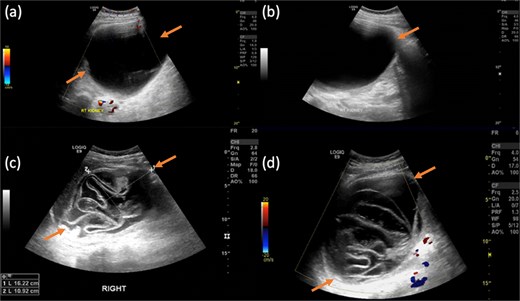

Pelvic magnetic resonance imaging (MRI) further characterized the pelvic lesion as a well-defined, non-enhancing, fluid-filled cyst measuring 3 × 2 × 1 cm without solid components, raising suspicion for pelvic hydatid seeding, although peritoneal inclusion cyst was also considered (Fig. 3). A 99mTc-dimercaptosuccinic acid (DMSA) scan showed preserved renal function with the right kidney contributing 25.7% of total function and a photopenic defect at the cyst site (Fig. 4). No other lesions were found on chest CT or brain MRI. Colonoscopy ruled out malignancy but revealed incidental low-grade adenomas.

Contrast-enhanced MRI of the pelvis in different sequences and different planes demonstrates a small, well-defined, oval-shaped lesion with high signal intensity on T2-weighted images (bold arrow—a and b) and low signal intensity on T1-weighted images (bold arrow—c). The lesion is located in the pelvis, inseparable from the seminal vesicles and the anterior rectal wall. It shows no signal drop on fat-saturated T2 sequence (bold arrow—d) no signify macroscopic fat, no restricted diffusion (dashed arrow—e and f) with T2 shine through, and no post-contrast enhancement on early subtracted (arrow head—g) and no delayed enhancement (arrow head—h). No solid component.